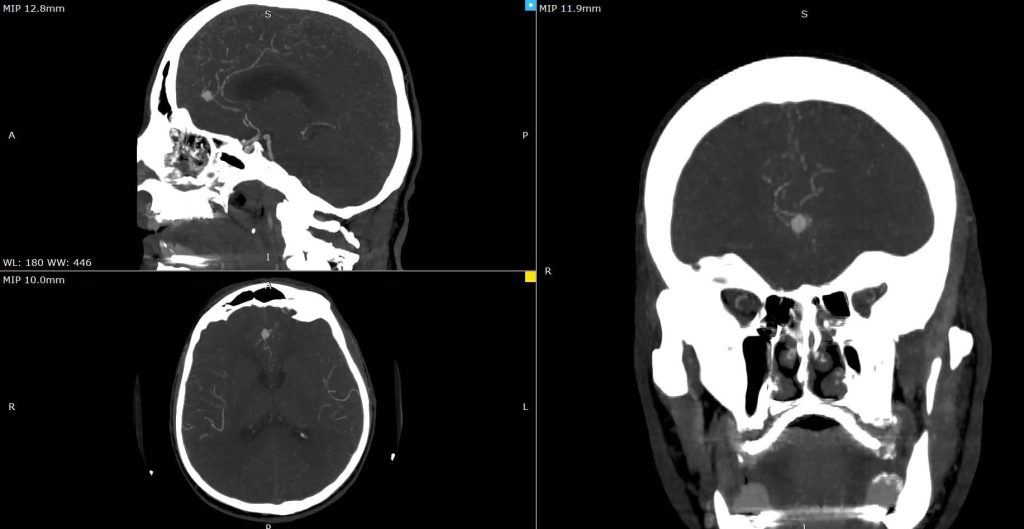

На Универзитетска клиника за неврохирургија беше извршена комплексна микрохируршка интервенција кај 57-годишен пациент со руптурирана аневризма на мозочен крвен сад.

Оваа иновативна метода претставува напредна техника која овозможува визуелизација на крвниот проток во реално време за време на операцијата.

– Со примена на контрастно средство, хирурзите можат прецизно да ја проценат проодноста на крвните садови и да го потврдат целосното исклучување на аневризмата, што е клучно за успешен исход, појаснува д-р Благој Шунтов, специјалист по неврохирургија и раководител на тимот.

Операцијата помина без компликации, а пациентот се опоравува без потешкотии. Примената на оваа напредна техника претставува значаен напредок во третманот на неврохируршки пациенти и потврдува посветеност на ЈЗУ УК за неврохирургија во примена на најновите медицински технологии.